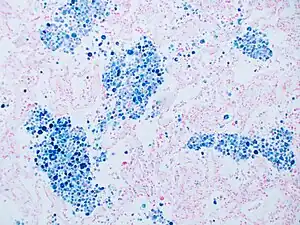

Stain for iron

Prussian blue is a common histopathology stain used by pathologists to detect the presence of iron in biopsy specimens, such as in bone marrow samples. The original stain formula, known historically (1867) as "Perls Prussian blue" after its inventor, German pathologist Max Perls (1843–1881), used separate solutions of potassium ferrocyanide and acid to stain tissue (these are now used combined, just before staining). Iron deposits in tissue then form the purple Prussian blue dye in place, and are visualized as blue or purple deposits.[37]

Histopathology of the liver, showing a Kupffer cells with significant hemosiderin deposition next to a hepatocyte with lipofuscin pigment. H&E stain.

Prussian blue staining, highlighting the hemosiderin pigment as blue.

Prussian blue stain